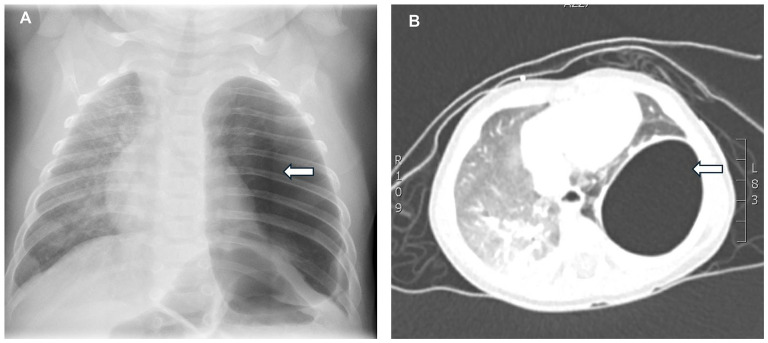

肺囊性病变在婴儿中并不常见,并且由于与其他囊性肺疾病的放射学特征重叠,可能会给诊断带来挑战。我们报告2例婴儿左肺囊性病变。最初的高分辨率计算机断层扫描(HRCT)提示鉴别诊断,包括气膨出、I型先天性肺气道畸形(CPAM)或孤立性囊性淋巴管瘤。通过左下叶切除术和病变切除后的组织病理学检查获得明确诊断。这些病例强调了准确诊断肺囊性病变的挑战,因为单独成像的局限性。

Pulmonary cystic lesions in infants are uncommon and can present diagnostic challenges due to overlapping radiologic features with other cystic lung conditions. We present 2 cases of left lung cystic lesions in infants. Initial high-resolution computed tomography (HRCT) suggested differential diagnoses, including pneumatocele, type I congenital pulmonary airway malformation (CPAM), or a solitary cystic lymphangioma. Definitive diagnosis was achieved through histopathological examination after left lower lobectomy and resection of the lesion. These cases highlight the challenges in accurately diagnosing pulmonary cystic lesions, given the limitations of imaging alone.